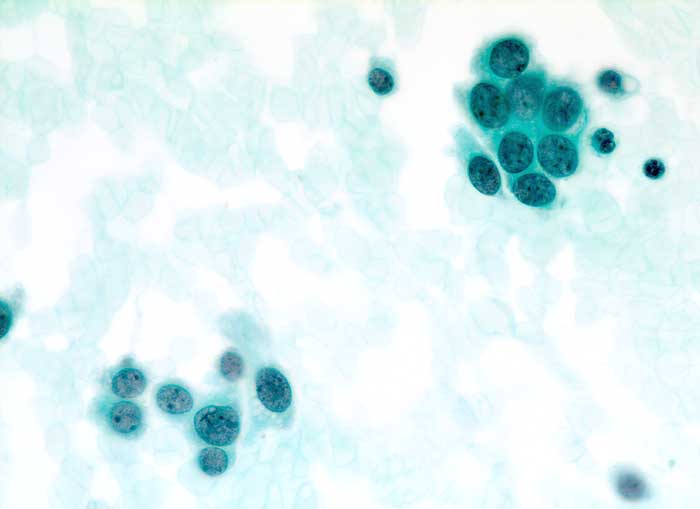

Duktales Carcinoma in situ

Feinnadelpunktion Mamma: Kleine Zellverbände. Die atypischen Zellen erscheinen monomorph und wenig grösser als normale Mammaepithelien.

Sonographisch wachsender Befund unklarer Dignität im oberen äusseren Quadranten rechts.

Zytologische Diagnose: Zahlreiche Karzinomzellen. Kommentar: Der zytologische Befund, insbesondere die Monomorphie der Tumorzellen passt gut zu einem duktalen Carcinoma in situ.

Zytologie

500